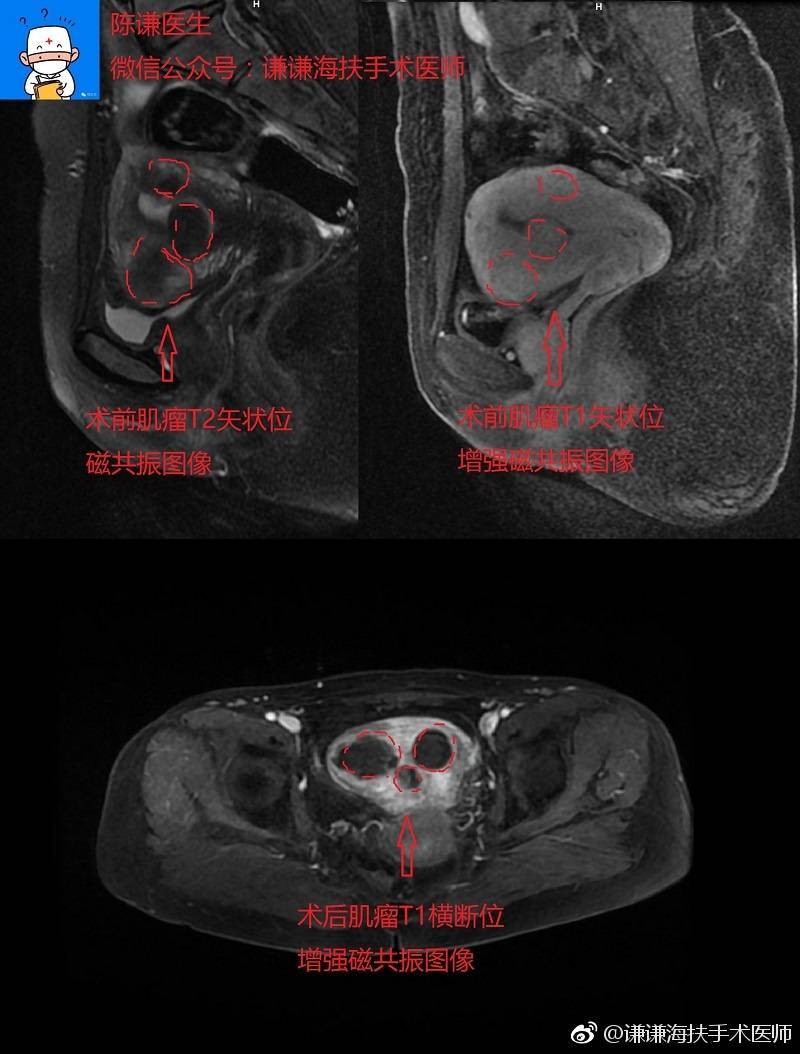

周某某子宫肌瘤海扶刀手术病例分享